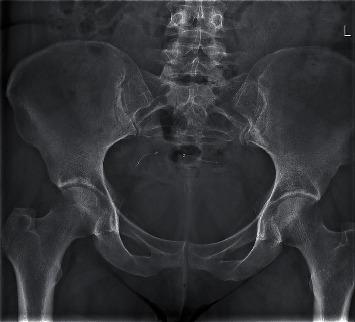

We present a case about Essure removal surgery in which the third markers of the device have torn off. The woman needed a second surgery for complete removal of the devices. Fluoroscopy during surgery is a good method to visualize the lost fragments. With fluoroscopy, a hysterectomy is not needed for complete removal. It is important to understand the structure of the device and to be aware of the four radiopaque markers during surgery and their removal.

我们介绍了一例关于取出Essure装置的手术病例,该装置的第三个标记物已脱落。该女性需要进行第二次手术以完全取出该装置。手术中的荧光透视是可视化丢失碎片的好方法。借助荧光透视,无需进行子宫切除术即可完全取出。了解该装置的结构并在手术过程中知晓四个不透射线的标记物及其取出情况非常重要。